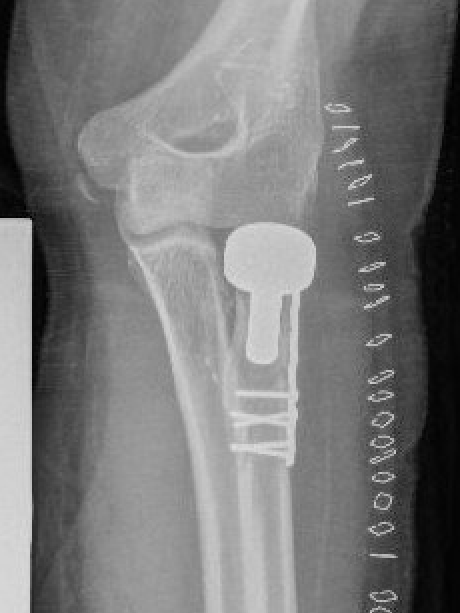

Completely displaced radial neck fracture

ORIF with plates

Acumed and Medartis Radial Head / Neck plates

Lateral approach

- identify safe zone (90 degrees between radial styloid) and Lister's tubercle)

- lag articular surface first if required

- pre-contoured low profile plates

- distal limit is bicipital tuberosity

- check ROM intra-operatively

- plates often bulky and may limit ROM

- close annular ligament